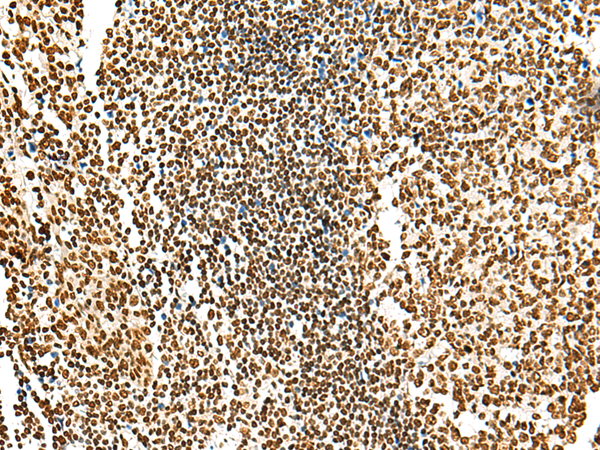

分类: 科研抗体货号: P13550别名: GSG2应用: IHC反应种属: Human